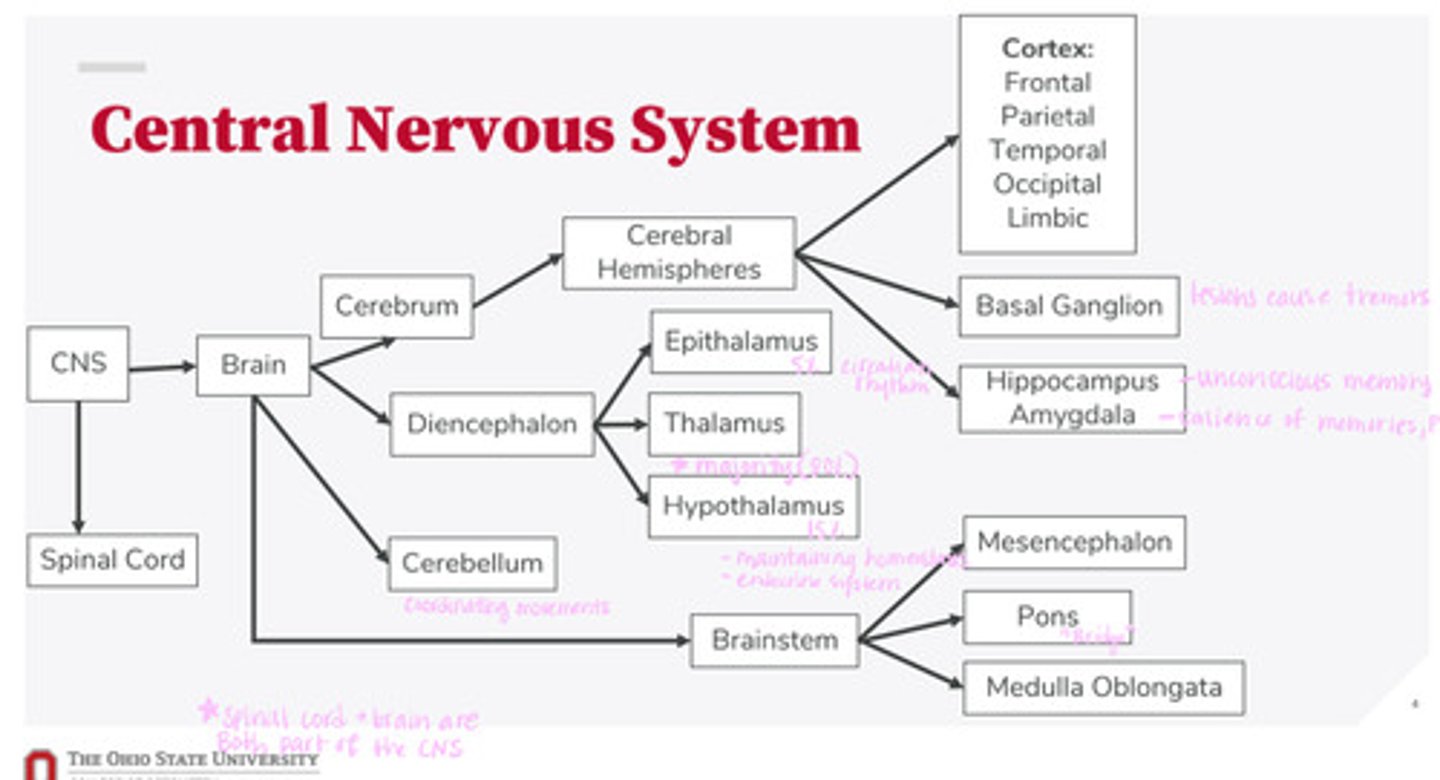

-brain

-spinal cord

What are the 2 divisions of the CNS?

-cerebrum

-diencephalon

-cerebellum

-brainstem

What are the 4 divisions of the brain?

-epithalamus

-thalamus

-hypothalamus

What are the 3 divisions of the diencephalon?

-mesencephalon

-pons

-medulla oblongata

What are the 3 divisions of the brainstem?

-cortex

-basal ganglion

-hippocampus

-amygdala

What are the divisions of the cerebral hemispheres?

-frontal lobe

-parietal lobe

-temporal lobe

-occipital lobe

-limbic system

What are the divisions of the cortex?

coordinating movements

What is the function of the cerebellum?

thalamus

A majority of signals from the diencephalon flow into where?

circadian rhythm

What is the function of the epithalamus?

-maintaining homeostasis

-endocrine system function

What is the function of the hypothalamus?

tremors

Lesions on the basal ganglion cause what?

hippocampus

What part of the brain is in control of unconscious memory?

amygdala

What part of the brain is in control of the salience of memories (PTSD)?

The bridge between the mesencephalon and the medulla oblongata

What is the function of the pons?